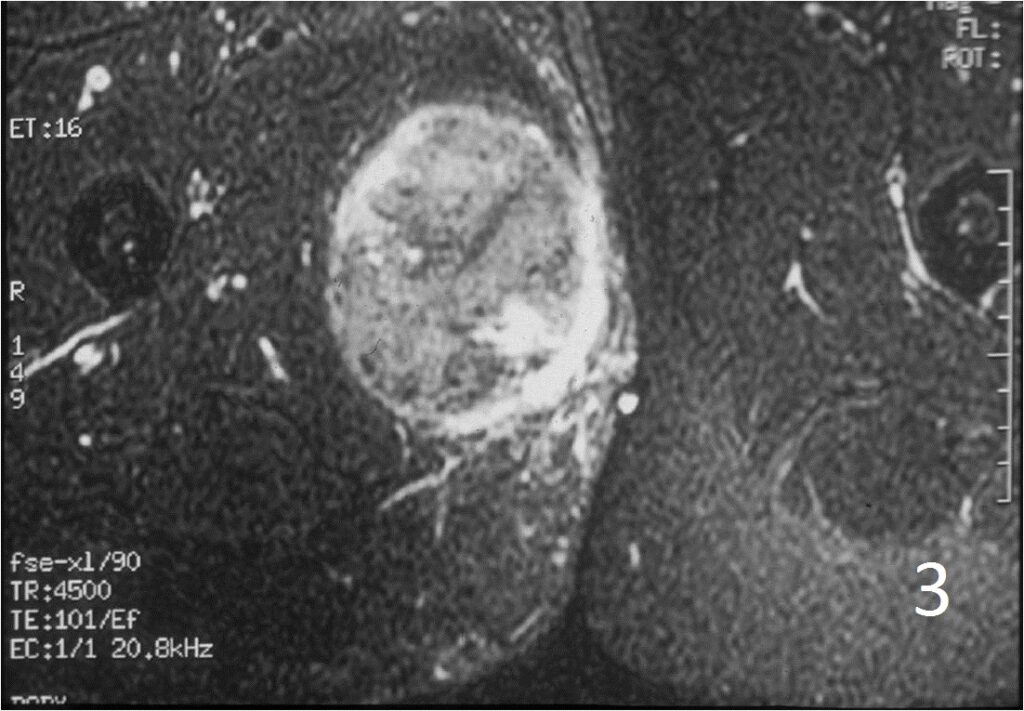

• Well defined heterogenous mass on T2W (Fig. 4, 9)

• Necrosis and hemorrhage are common, especially in high grade tumors

Fig. 2-4: An MRI of the thigh shows a mass in the medial compartment that is isointense to muscle on T1W images (Fig. 2) and heterogeneous on T2W (Fig. 3). Sagittal T1W post contrast with gadolinium demonstrates enhancement of the tumor (Fig. 4).